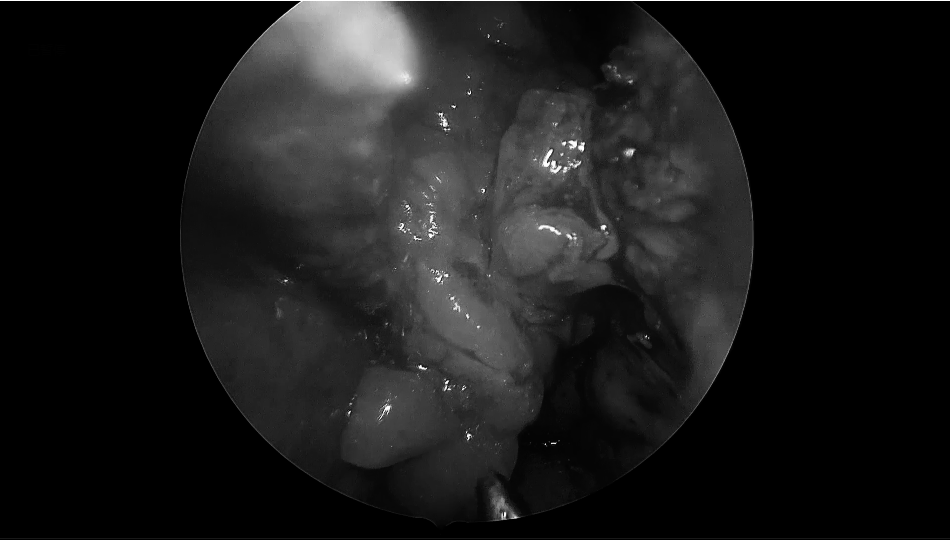

▼内镜探查瘤腔,镜下全切